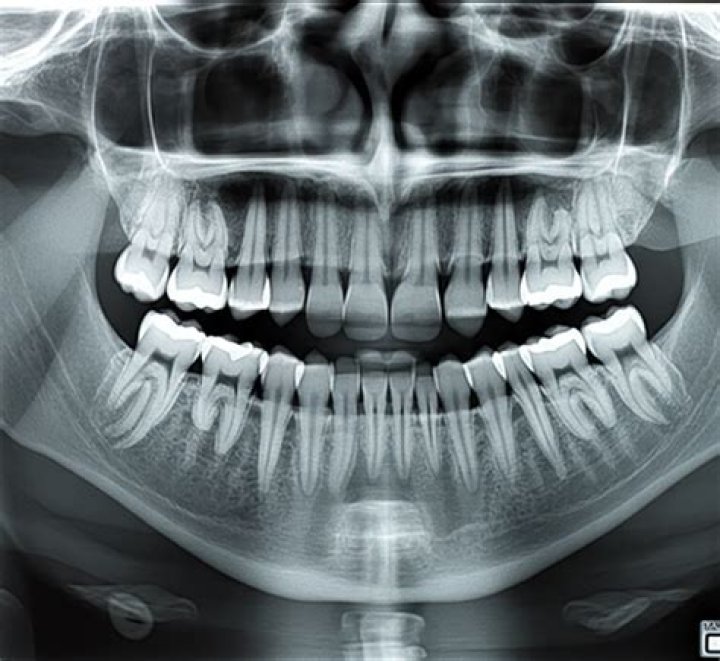

What does a dental X-ray show?

Dental X-rays are pictures of the teeth, bones, and soft tissues around them to help find problems with the teeth, mouth, and jaw. X-ray pictures can show cavities, hidden dental structures (such as wisdom teeth), and bone loss that cannot be seen during a visual examination.

What is periapical image?

A periapical image shows the area completely “around the apex.” This is important in that if the pulp tissue inside the tooth is not healthy, it will produce a dark shadow at the apex of the root which can only be seen with this type of radiograph. At right is a periapical film.